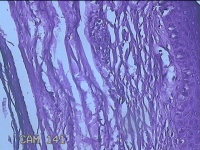

左眼外侧缘上肿物

性别

女

年龄

60岁

临床诊断

痣;疣

左眼上睑缘白色丘疹1年余。

灰白粉红色肿物0.8x0.3x0.2cm两个,表面光滑。